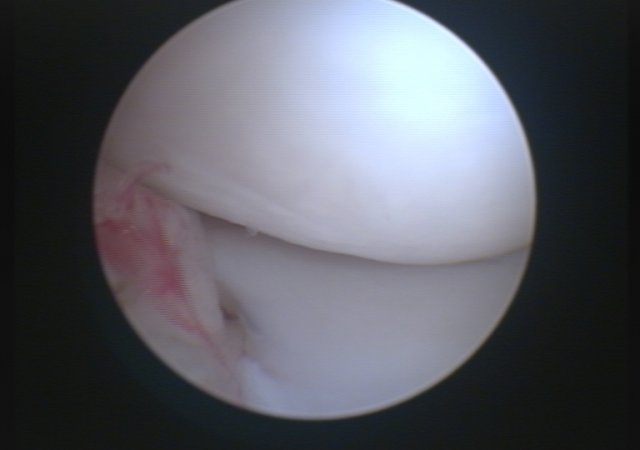

In unserer Praxis bieten wir mit der Arthroskopie die minimalinvasive Möglichkeit auch Anrisse des vorderen Kreuzbandes sicher zu diagnostizieren und gleichzeitig den häufig mitbetroffenen Meniskus zu untersuchen und zu operieren.

Arthroskopie gerissenes Kreuzband

Arthroskopie Meniskus Nahaufnahme

Arthroskopie Meniskus